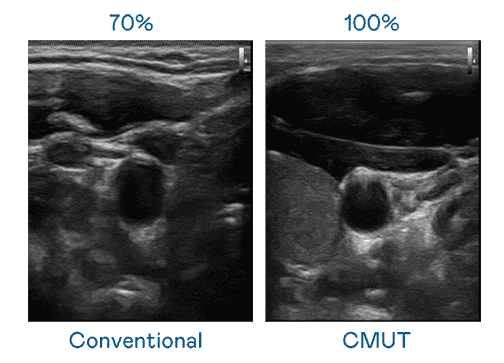

CMUT 技术是一种用电容式微机电元件来产生超音波讯号的技术。。。与传统 PZT 压电式技术相比,,CMUT 频宽增加 30%,,,更宽频的超音波讯号让影像解析度大幅提升,,,是实现高影像品质医疗超音波扫描、、、、促进精准医疗发展的关键技术。。。。

超音波影像的解析度高低,,首先取决于探头能发出的讯号频宽。。。。彩运网 CMUT 可提供高清晰的超音波讯号,,,提供高频宽、、高灵敏度、、、、影像纹理细节更高的超音波影像,,协助医护人员缩短影像判读时间及利用精准的医疗影像进行诊断。。。